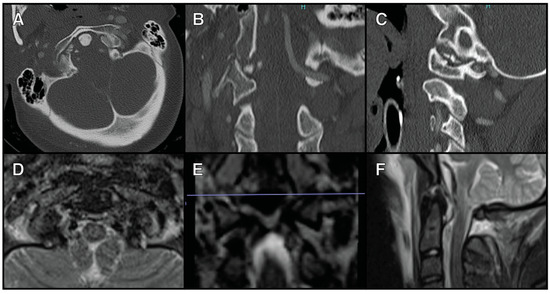

The second patient was a 27-year-old male who presented after a fall from a scooter. He had a left type III OCF with obvious coronal deformity. MRI showed the disruption of the left alar ligament and the transverse cruciate ligament (Figure 2). He underwent an O-C2 fusion. Neither of these patients had any neurological deficits.

Figure 2. A 27-year-old male who presented after a fall from a scooter with a left type III OCF. (A) The axial view of a CT cervical scan showing the left type III OFC. (B) The coronal view of a CT cervical scan showing the left type III OFC and the coronal deformity. (C) The sagittal view of a CT cervical scan showing the left type III OFC. (D) The axial view of an MRI cervical T2 STIR sequence showing left alar ligament disruption. (E) The axial view of an MRI cervical T2 STIR sequence showing transverse cruciate ligament disruption.